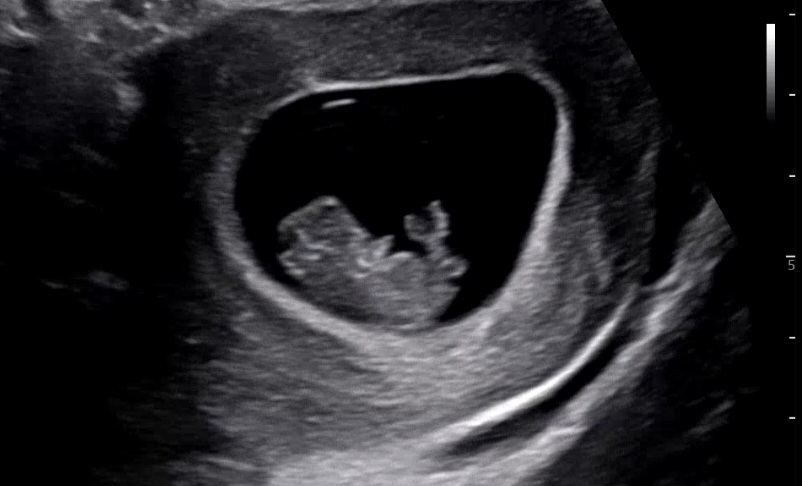

9주차 젤리곰

초음파를 대자마자 짧은 팔다리를 휘적휘적 너무 웃겼네요ㅋㅋ 벌써 무대체질인걸까요? 엄마는 입덧으로 하나도 못먹어서 기력이 없었는데, 웃긴게 초음파보니까 또 힘이나네요ㅎㅎ 입덧약이 마침 다먹어서 2일 생으로 보냈는데 와... 밤에 체덧에 담날 토덧까지... 먹으면 체하고 토해요 ㅠㅠ 오늘 약 추가로 받아왔네요.. (진료 기다리다가도 마카롱 작게 한입먹고 토하고 후...) 의사선생님은 약을 그냥 멈추지말고 계속 먹으라고 하더라구요~ 상상도 못한 입덧에 힘들지만! 우리 엄마들 화이팅입니다!

ㅎㅎ짧은 팔다리 휘적이 진짜 귀엽고 웃겨섴ㅋㅋ 힘이 나더라구요!! 뱃속에서 헤엄치고 있나봐요 ㅎㅎ